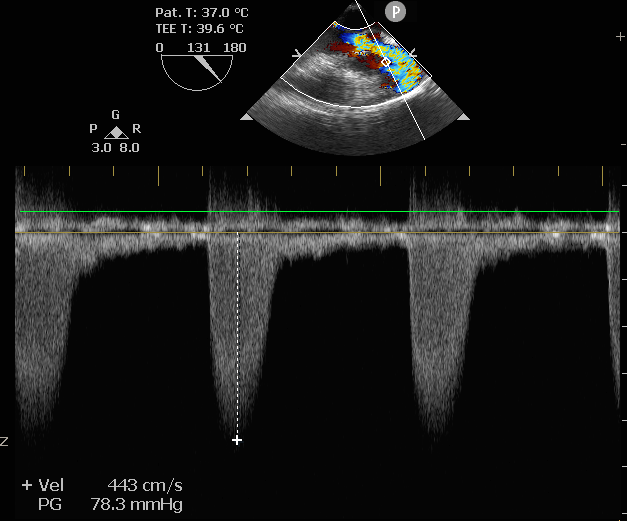

术后即刻评估

术后压差从78.3mmHg降至6.89mmHg,瓣膜正常工作,患者血流动力学即刻得到改善。